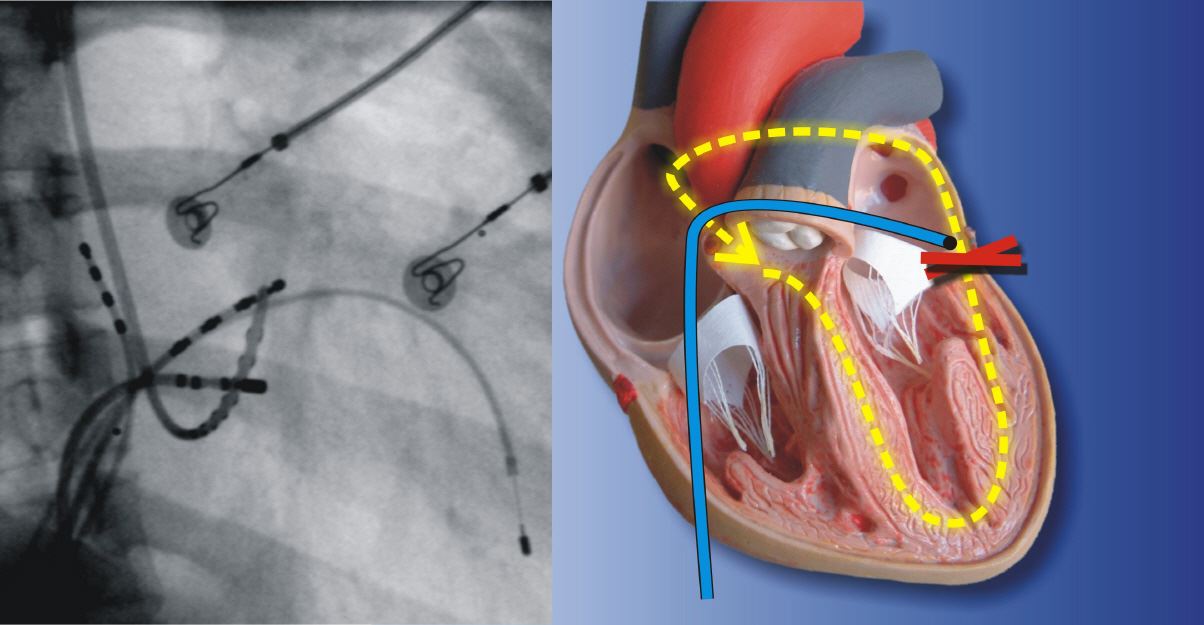

Katheterablation: trotz hoher Erfolgsquote zu riskant

Die Katheterablation ist ein invasiver Eingriff, bei dem Katheter in das Herz eingeführt werden, um die abnormen elektrischen Signale zu isolieren und zu eliminieren.

Obwohl dies eine effektive Behandlungsoption sein kann, birgt sie auch Risiken wie Blutungen, Infektionen und Schädigungen an umliegenden Geweben.

Es ist auch schon vorgekommen, dass Patienten aufgrund der entstandenen Blutungen leider gestorben sind.

“Zudem ist die OP nicht ganz billig und die Ablation kann schnell mehr als 10.000€ kosten. Die meisten Krankenkassen übernehmen keine Kosten.